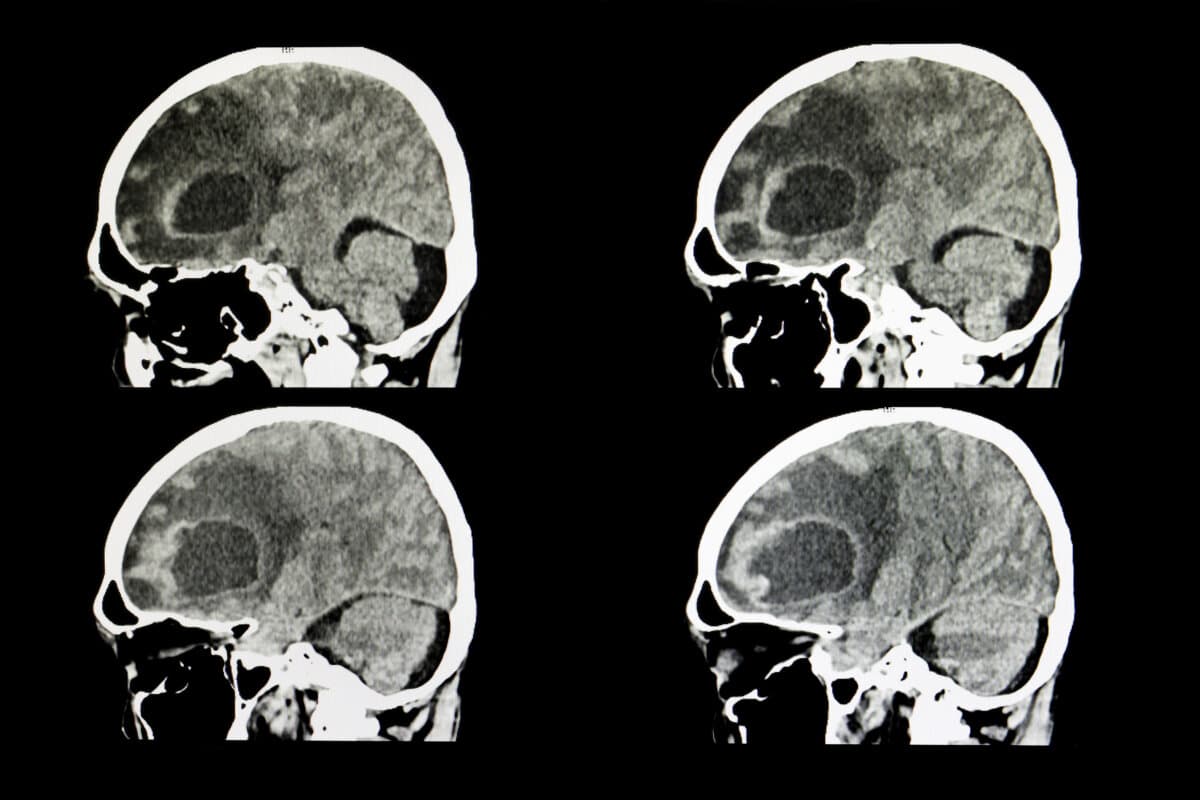

ÖGN: Neue Optionen in der Therapie von Gliomen

Gliome und insbesondere Gliobastome waren von den rasanten Entwicklungen, die die Onkologie in den vergangenen Jahren durchgemacht hat, weitgehend ausgenommen, was sich in einer unverändert ungünstigen Prognose niederschlug. Nun sind Veränderungen absehbar und gezielte Therapien könnten vermehrt auch bei Hirntumoren zum Einsatz kommen.